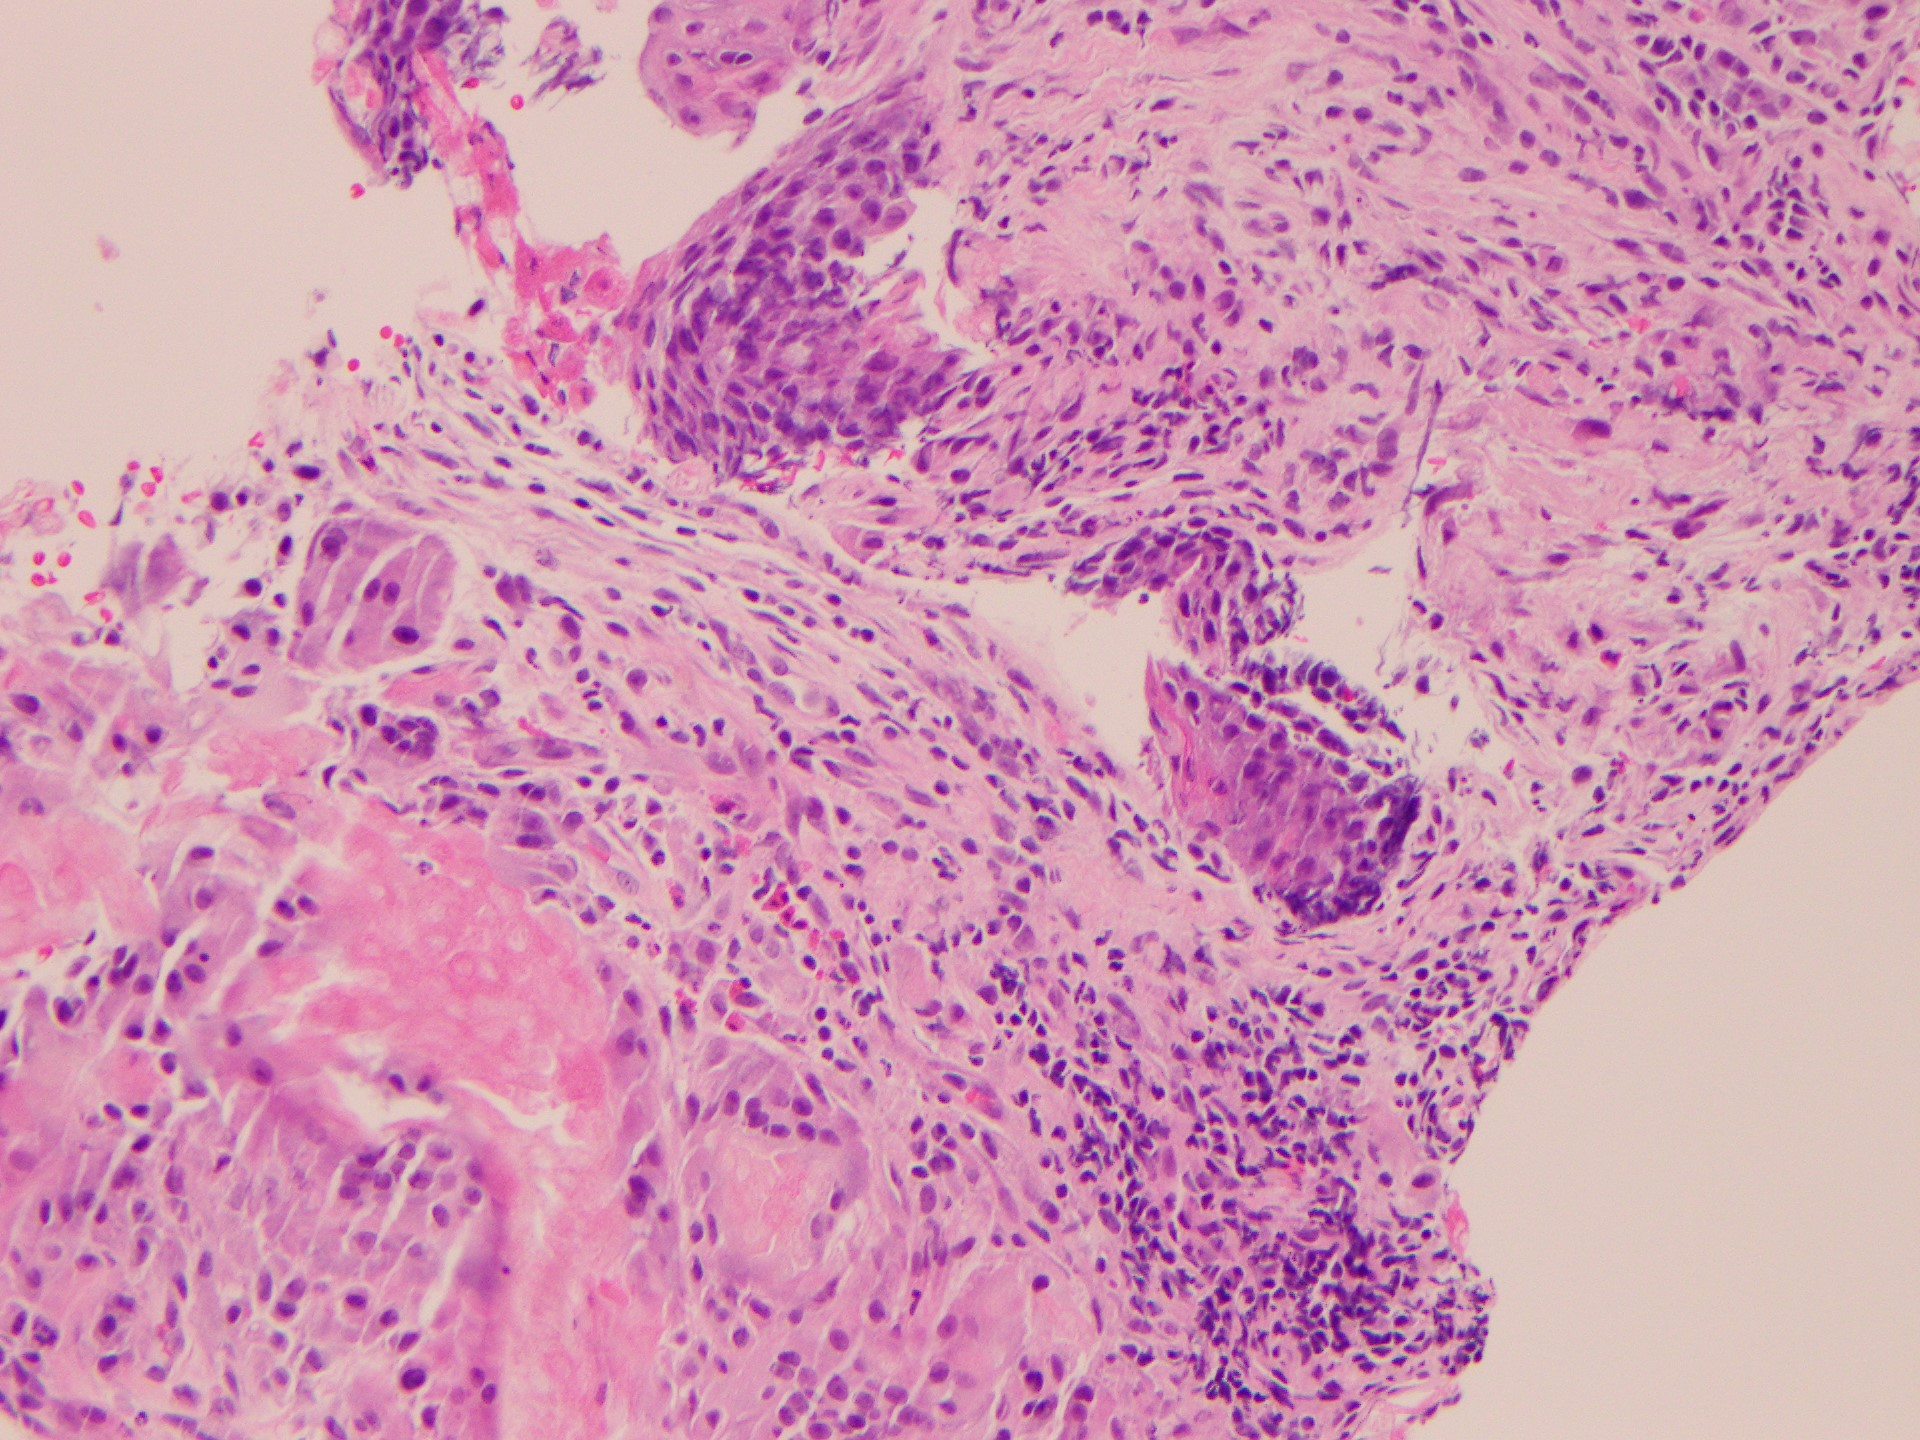

The ultrasound-guided biopsy was negative for malignancy, but the results revealed fragments of pilomatricoma (Figures 2 and 3).

Figures 2 and 3. Anucleated ghost (or shadow) cells with foreign-body reaction at the periphery (hematoxylin-eosin, original magnification ×40).